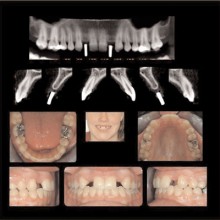

ORTHODONTIC RECORDS: The greatest recent innovation has been the inclusion of the spatially true-size three-dimensional digital image data into the orthodontic records. Ultimately the three-dimensional records will replace the two-dimensional records. The current generation cone beam CT promises to produce, in a single scan, enough information to eliminate the need for conventional panoramic, occlusal, cephalometric, selected periapical, and tempormandibular-joint tomographic studies and possibly plaster dental models. The CBCT data will be superior to that gained from the compiled series of two-dimensional images, and the absorbed dose will be less.

The anatomy sets some of the boundary conditions for tooth position. The identification and visualization of these boundary conditions can be performed by applying volumetric CT during initial workup. There are clinical instances when tooth movement is prevented or diminished because of anatomic boundaries, such as cortical margins, adjacent teeth, and dense bone. In addition, expansion of the dental arch form or tooth torque may be limited or confined by the labial and buccal cortical margins of the alveolar bone. These boundaries are difficult to visualize without the aid of cross sectional or three-dimensional imaging techniques (Figure 9).

With the traditional two-dimensional dental-imaging series some areas of anatomy are poorly visualized. These three-dimensional scans can give valuable information about other areas of the dentition such as the position of the upper incisor roots relative to the lingual cortical border of the palate to plan retraction, the amount of bone available in the posterior maxilla available for distalization, the amount of bone lateral to the maxillary buccal segments available for dental rather than skeletal expansion, airway information on the pharynx and nasal passages, upper root proximity to the maxillary sinus, the three-dimensional extent of an atrophied alveolar ridge, or the position of the lower incisor roots in bone. These scans also allow three-dimensional visualization of bony defects and supernumerary teeth in patients with cleft lip and/or palate. Additionally, axially corrected tomograms of the temporomandibular joints can be obtained from the same scan. The ability to visualize an axially corrected view of the temporomandibular joints with the teeth in occlusion on the same reconstructed section is one significant advantage of the volume scan. Therefore, there is substantial “value-added” imaging benefits to these scans for complicated orthodontic patients.